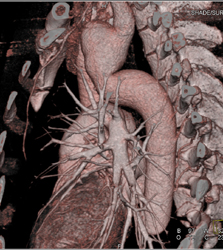

Diagnosis

Diseased LAD